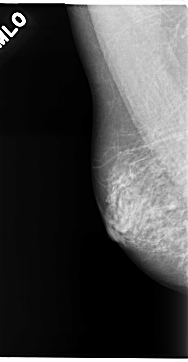

C_0141_1.RIGHT_MLO

RIGHT_MLO LINES 4704 PIXELS_PER_LINE 2440 BITS_PER_PIXEL 12 RESOLUTION 50 NON_OVERLAY